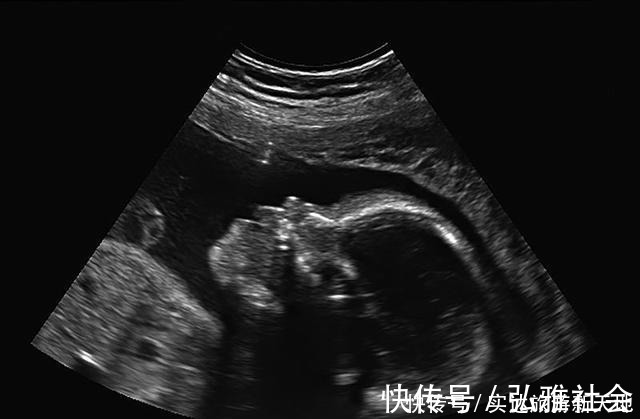

2、宝宝的NT检查数值NT检查是指宝宝颈部的空隙位置的颈项透明层厚度。正常情况下,这里应该是透明的,因为这是宝宝新陈代谢所产生的积液,是对宝宝的一种保护。NT检查目的是在孕妇怀孕初期来诊断宝宝是否有染色体疾病,比如21三体综合征等胎儿异常,是早期排除宝宝是否发育正常的检查。

NT检查一般在孕妇怀孕3个月左右去做的检查。宝宝NT的正常厚度是要小于3mm的。如果NT检查的结果显示厚度大于3mm,这就警示我们要注意:胎儿发育可能不是那么健康。在检查报告中,一般也会显示胎儿的染色体是否存在异常现象,胎儿发育是否健康,没有畸形。孕妇后面还会做唐氏筛查来排查宝宝是否发育良好,医生也会重点关注,必要时孕妇可以多做些检查综合判断,例如无创DNA检查、羊水穿刺检查、胎儿染色体检查等。